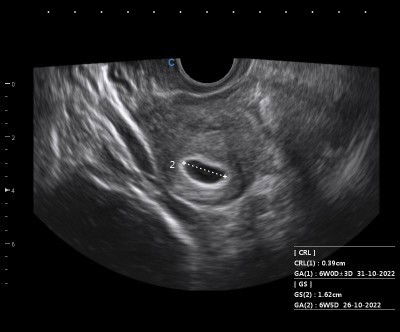

Usg melihat kantong janin

Bun mau tanya kemarin sy usg biar tau ada kantong nya atau blm nah udh kliatan bun.tp sy bingung untuk hpl mana yg tepat y bun tgl 26/10 atau 31/10 ??